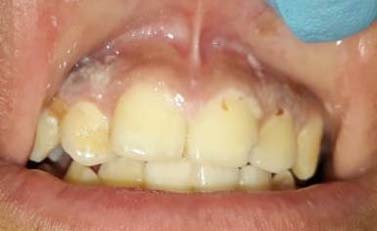

In the examination of soft tissues, we found that 80% of patients with T1DM or B-cell ALL presented some type of oral alteration; 100% of the healthy group were free of pathology (Table 4). The lesions found in patients with T1DM (Figure 1)were gingivitis (40%) (Figure 2) and traumatic ulcers (40%) (Figure 3). In patients with B-cell ALL predominated: candidiasis (40%) (Figure 4), gingivitis (20%) (Figure 5), HSV-likeulcers (20%) (Figure 5), traumatic ulcers (20%) (Figure 6), mucositis (20%) (Figure 6). Therefore, lesions in the B-cell ALL patients group were more variable than in the T1DM one; moreover, not only a greater variability but also a biggerlesions intensity were observed in the B-cell ALL group.

B-cell ALL group also presented a greater quantity and variety of lesions which were more severe. Like in T1DM, it was detected gingivitis and traumatic ulcers along with exfoliative cheilitis (Figures 5 and6)and other lacerations: oral candidiasis (Figure 4), herpeticulcers (Figure6), and mucositis (Figure 6). Basing us on the underlying disease's natural history, treatment, and BC results, we suggest that the most relevant lesion-generating factor was the immunosuppression state in this group. So, oral alterations secondary to B-cell ALL pathophysiology can be explained as follows: